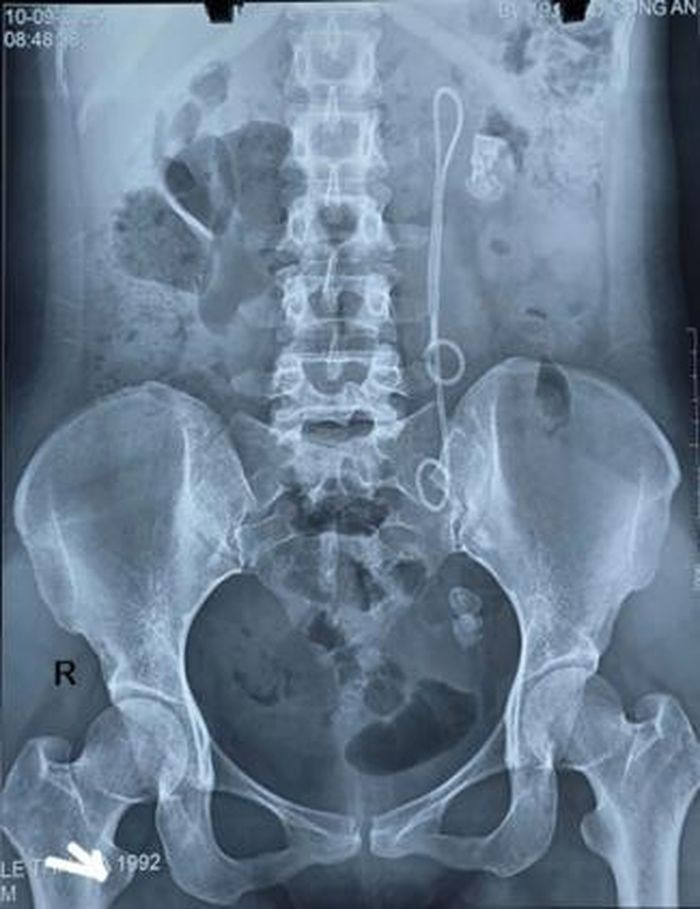

Hình ảnh XQ của bệnh nhân. Ảnh: Bệnh viện 19-8

Qua thăm khám lâm sàng và cận lâm sàng, bệnh nhân được chẩn đoán sỏi thận trái và sỏi niệu quản trái đoạn 1/3 dưới. Đặc biệt, bệnh nhân còn Sonde JJ (một thiết bị y tế) đặt 15 năm chưa rút.

Trường hợp này, do Sonde JJ tồn tại tới 15 năm, bệnh nhân xuất hiện sỏi to ở nhiều vị trí, Sonde bám sỏi và di chuyển bất thường, khiến quá trình điều trị phức tạp, tiềm ẩn nhiều nguy cơ.